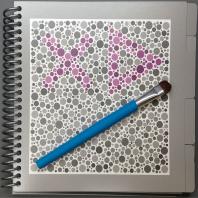

- eFig. 9-21 - Une des planches de l'album HRR